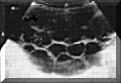

Theca-lutein

cysts

are

the

ovarian

response

to

excess

human

chorionic

gonadotropin

(hCG)

secretion

by

GTNs.

These

formed

large

follicles

that

full

of

liquid

and

have

smooth

walls,

partially

or

totally

occupy

ovaries

(Picture2).

Picture2.

cysts.